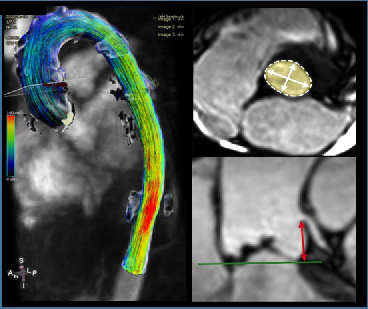

Cardiovascular MR Imaging

Agnes Mayr, Christian Kremser, in cooperation with the Department of Cardiology

a) STEMI CMR: CMR Parameters of Myocardial Tissue Damage in ST-Elevation Myocardial Infarction (STEMI).

Since 2005, almost 900 patients have been examined under a comprehensive cardiac MRI (CMR) protocol within the first week as well as 4 months, 12 months and 10 years after acute STEMI. In more than 60 internal original papers, CMR myocardial infarction severity markers were assessed and the effects of CMR on optimised risk assessment shortly after STEMI were evaluated.

b) TAVI CMR: CMR to Guide Transcatheter Aortic Valve Implantation (TAVI).

This ongoing randomised study investigates the non-inferiority of TAVI CMR to TAVI CT for the first time, with regard to efficacy and safety end-points in the guidance for TAVI evaluation.

c) 4D Phase Contrast Flow Measurements

- Patients with different grades of aortic valve stenosis: comparison of 4D flow-assessed stenosis severity with 3D echocardiography and invasive measurements.

- Patients with cryptogenic stroke: recording turbulent kinetic energy, changes in flow patterns and regional wall stresses as well as occurrence of a vortex-shaped flow along the thoracic aortic wall, in order to optimise the elucidation of potential cardioembolic sources.